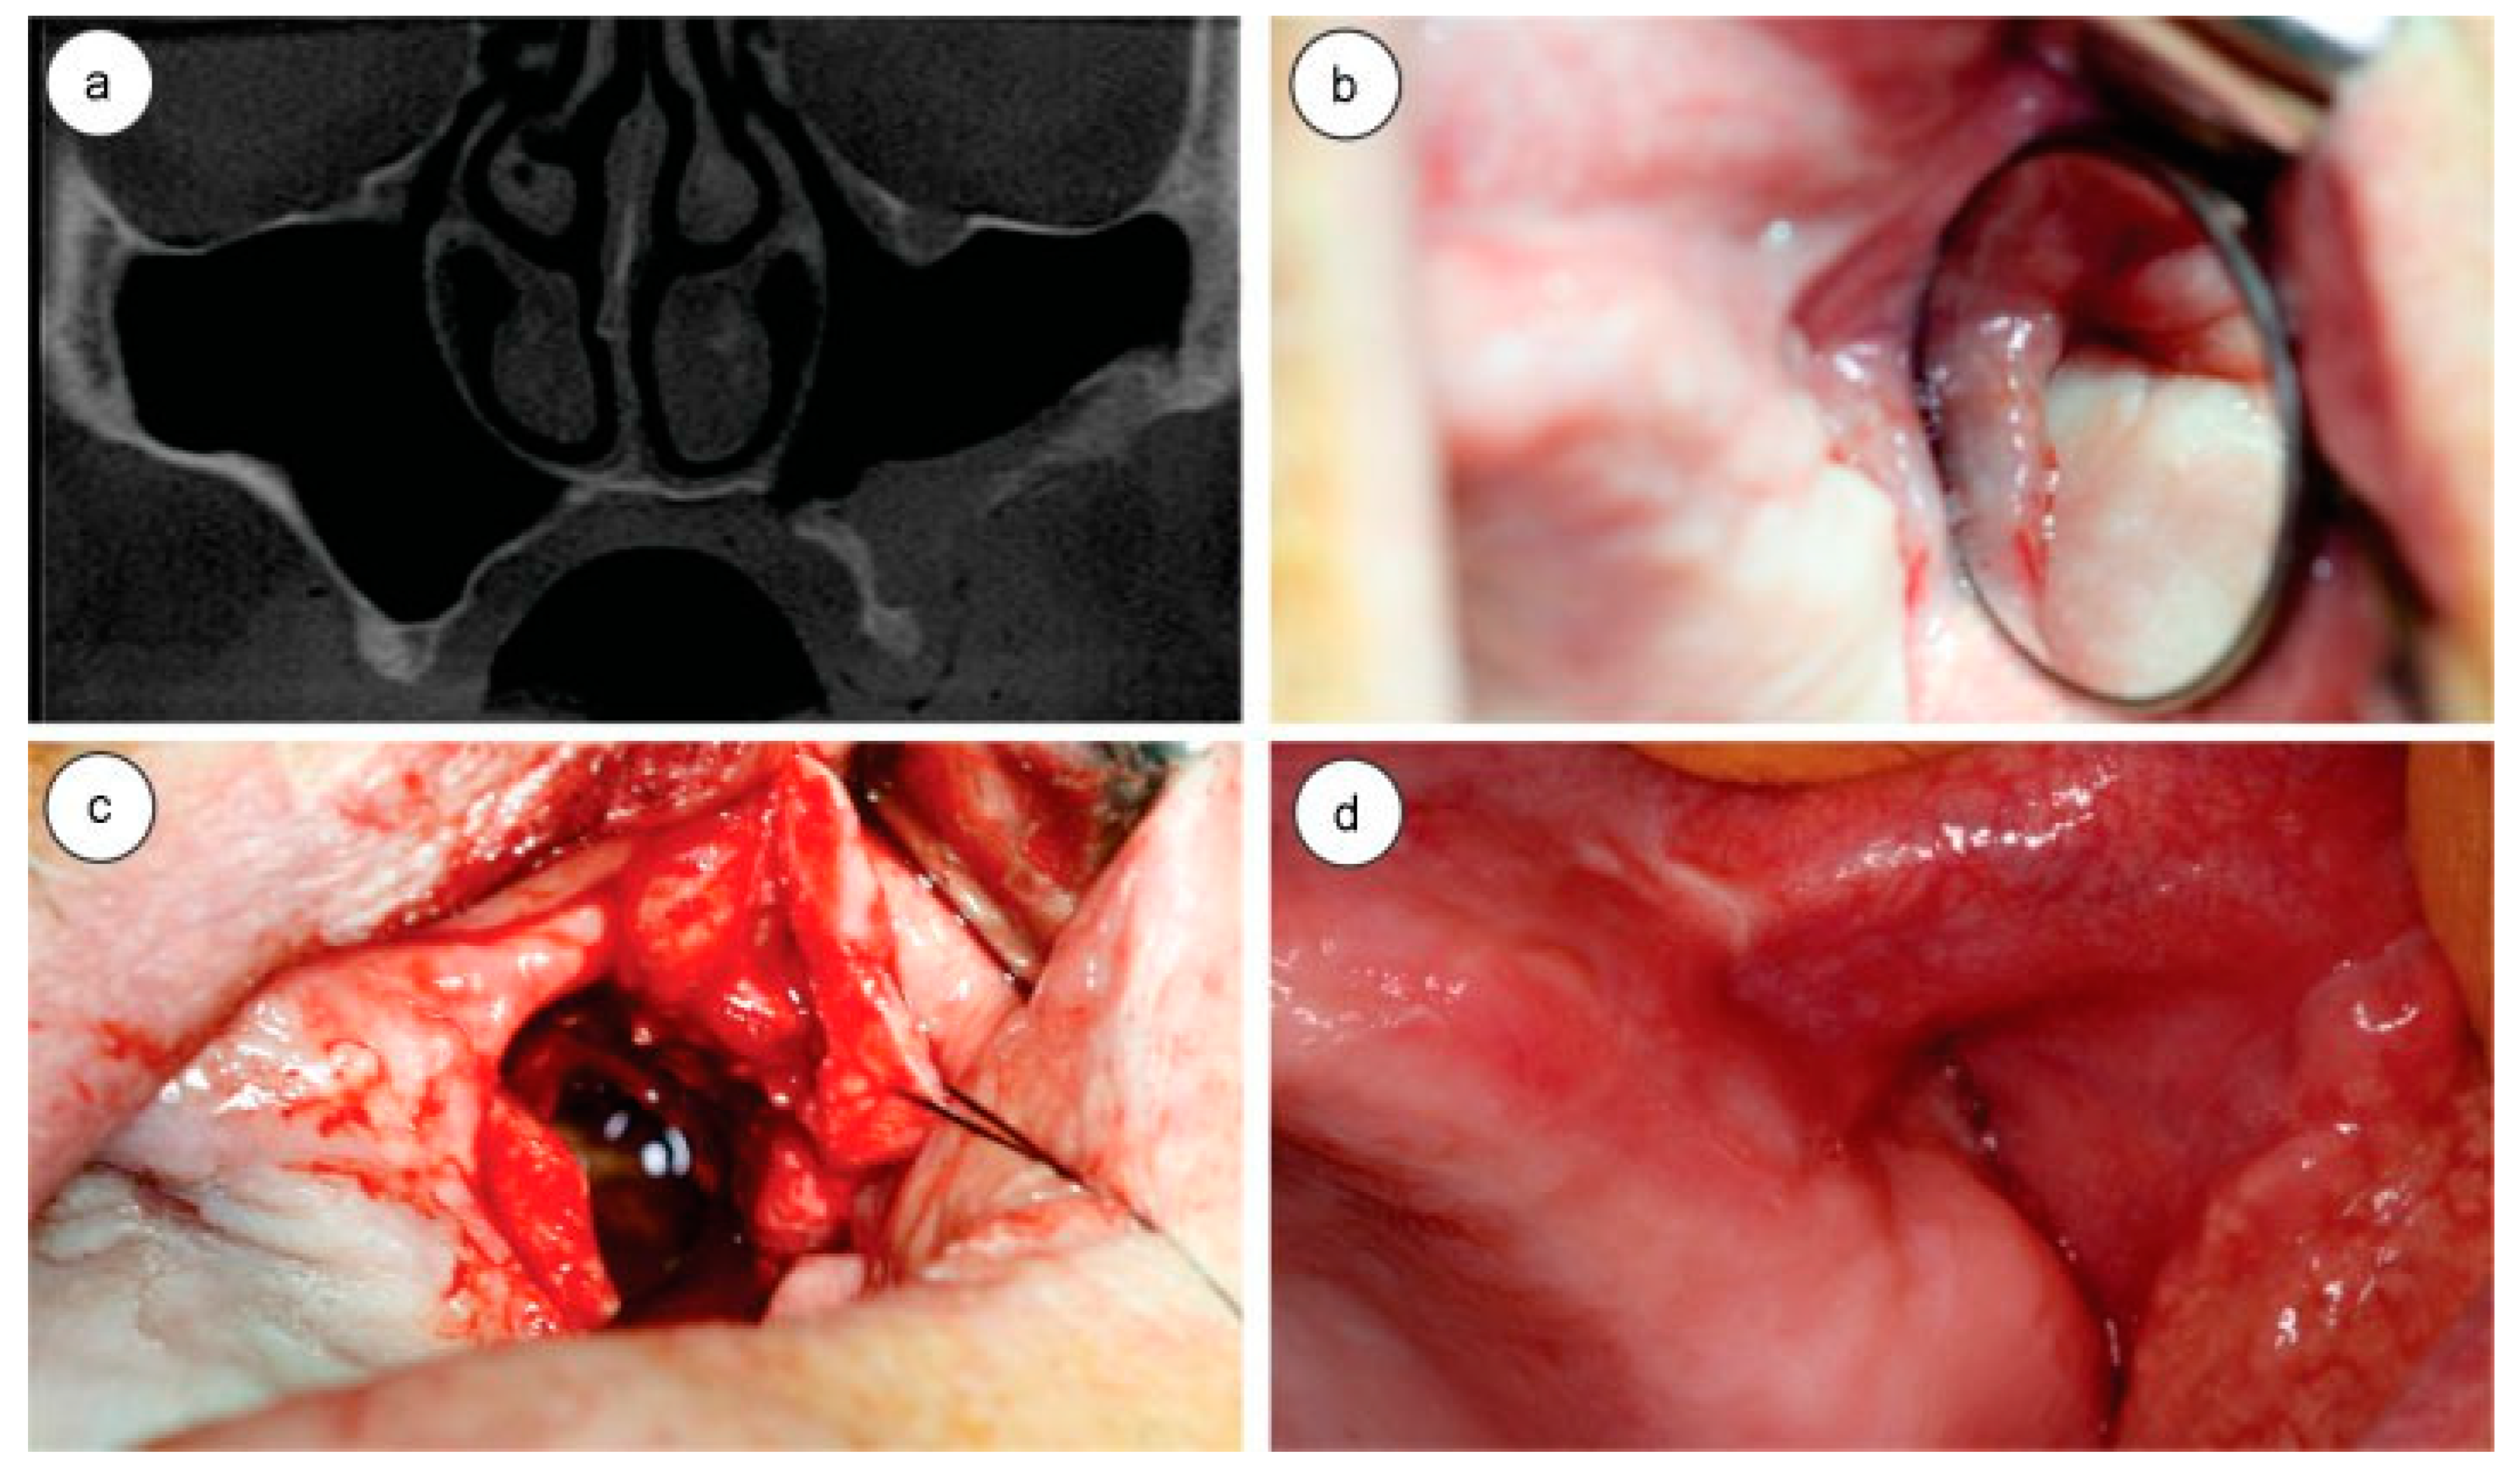

Left-sided facial scars without evidence of changes that could point to the occurrence of an acute infectious process were observed in the extraoral physical examination. The intraoral examination revealed total upper edentulism and the use of a dental prosthesis; the presence of an oroantral fistula with spontaneous purulent drainage and bulging of the area was observed in the posterior area of the left maxilla. The lack of bone support at the bottom of the vestibular sulcus and a mild discomfort during the procedure were observed during palpation. The patient showed signs and symptoms consistent with chronic sinusitis. A cone beam computed tomographic (CT) scan of the maxilla and paranasal sinuses was performed, revealing the presence of foreign bodies lodged in the roof and the medial wall of the left maxillary sinus, with morphological characteristics of teeth. Also, the sinus was veiled, confirming the diagnosis of chronic sinusitis, in this case caused by foreign bodies (Figure 1a,b). The patient had no change in visual acuity or ocular mobility due to the presence of the teeth in sinus roof/orbital floor.

Although literature recommends the use of an endoscope in relation to direct access or the Caldwell-Lucprocedure [14,15], the access was chosen due to the possibility of direct visualization of the surgical site, the size and location of foreign bodies, as well as the unavailability of an endoscope in the department. An incision in the alveolar ridge (due to decreased alveolar height), exposure and removal of the anterior part of the maxillary sinus, and the removal of the dental elements located on the medial wall and roof of the maxillary sinus were performed. After inspecting the interior of the maxillary sinus to rule out the presence of any other foreign body, the sinus mucosa was removed and sent for histopathological examination, which revealed a cyst of inflammatory nature. The flap was repositioned and sutured with 4.0 resorbable Vicryl wire (Figure 1c,d).

Figure 1. (a) Computed tomography (CT) axial slice, arrows are showing the teeth in maxillary sinus; (b) CT coronal slice showing the teeth in maxillary sinus roof; (c) surgical approach showing the tooth; (d) teeth and removed tissue.